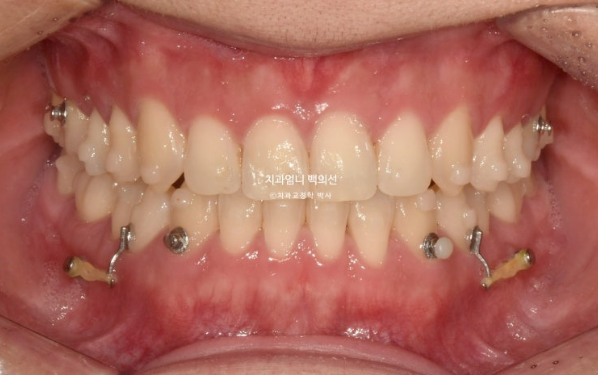

You can see a well-aligned midline and a good bite.

If the molar bite is not perfect, we do not finish treatment.

This is how it looks with the wire retainer in place.